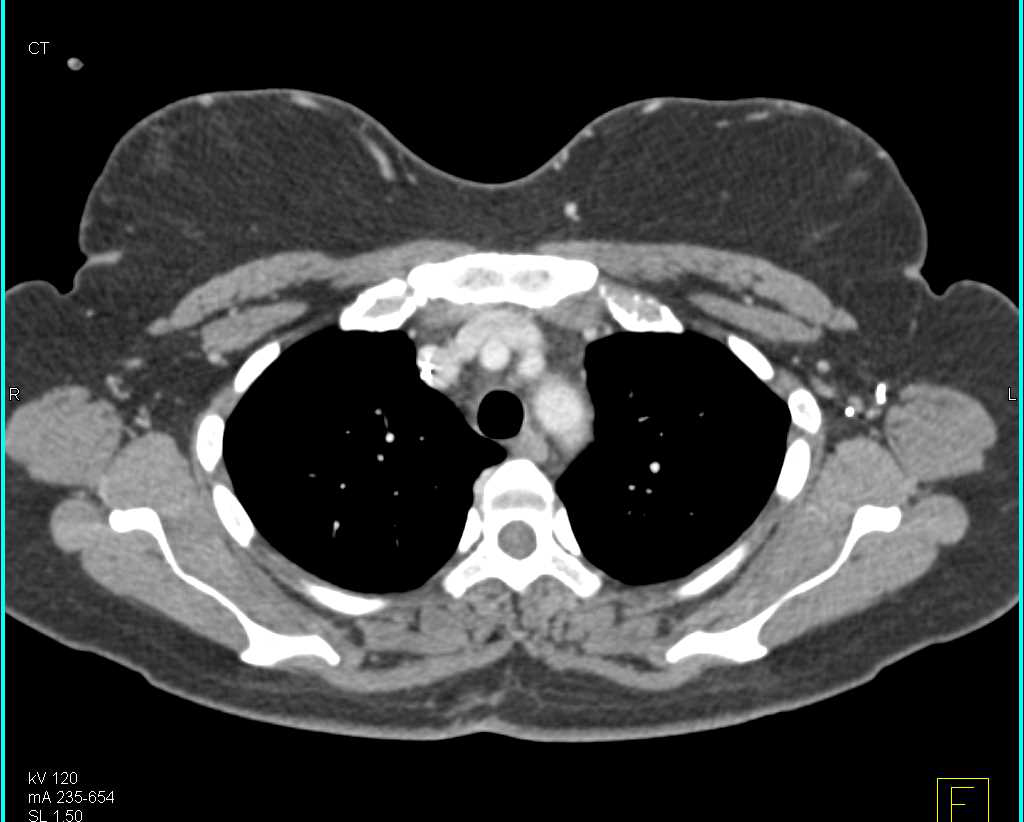

Subtle Breast Cancer with Multiple Nodules